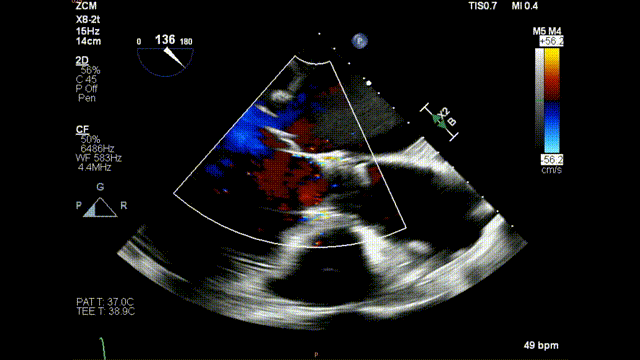

术前食道超声-长轴color

术前食道超声-长轴 color

术后食道超声示:

术后食道超声-短轴color

术后食道超声-长轴color